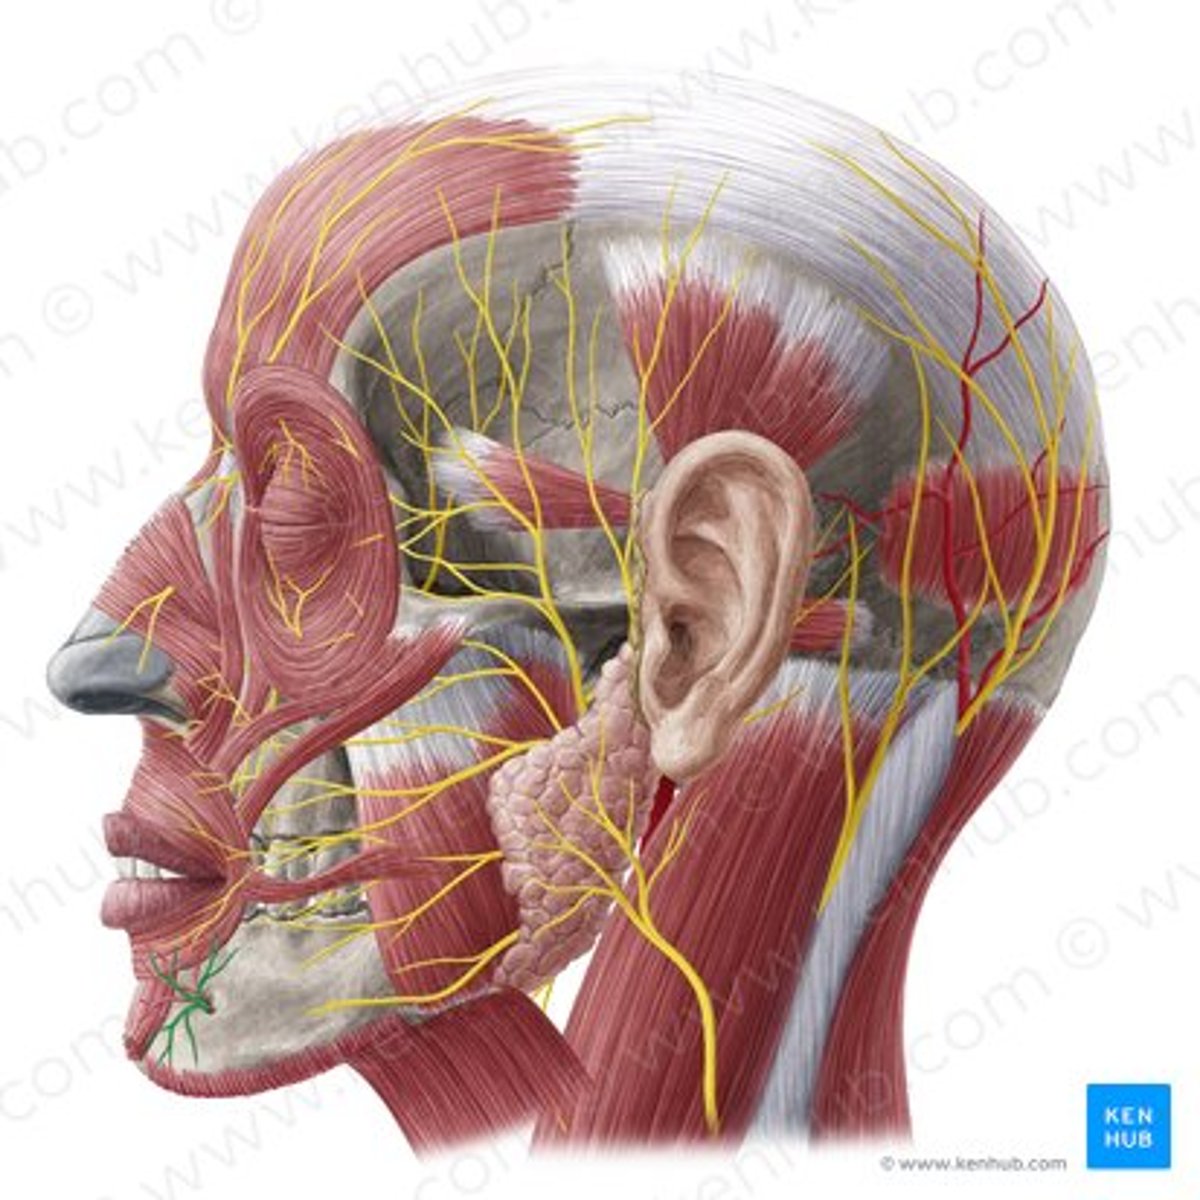

facial nerve (CN VII)